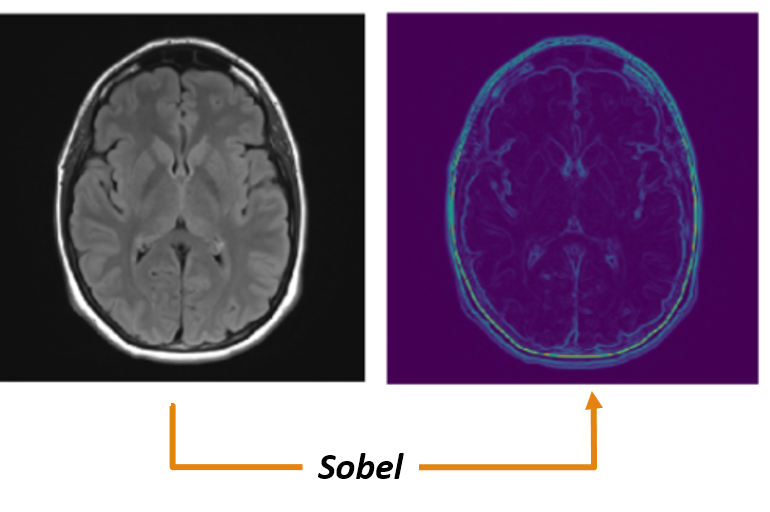

(b) Sobel edge detection for gray scale MRI image.

Figure 6: An example of special preprocessing technique.

Sobel edge detection: Sobel edge detection technique is highly efficient in the detection of edges in images if the image is free of granular noises. Modified Sobel edge detection techniquesgao2010improved proved to perform superior in certain conditions. In this experiment, after the basic preprocessing of the MRI, granular noise is certainly removed in the Gaussian filtering process. Hence, we can proceed with the basic Sobel edge detection technique vijayarani2013performance ; vincent2009descriptive for detection of edges present in the MRI images. An example showing the Sobel edge detection for an MRI sample is shown in Figure-6(b).